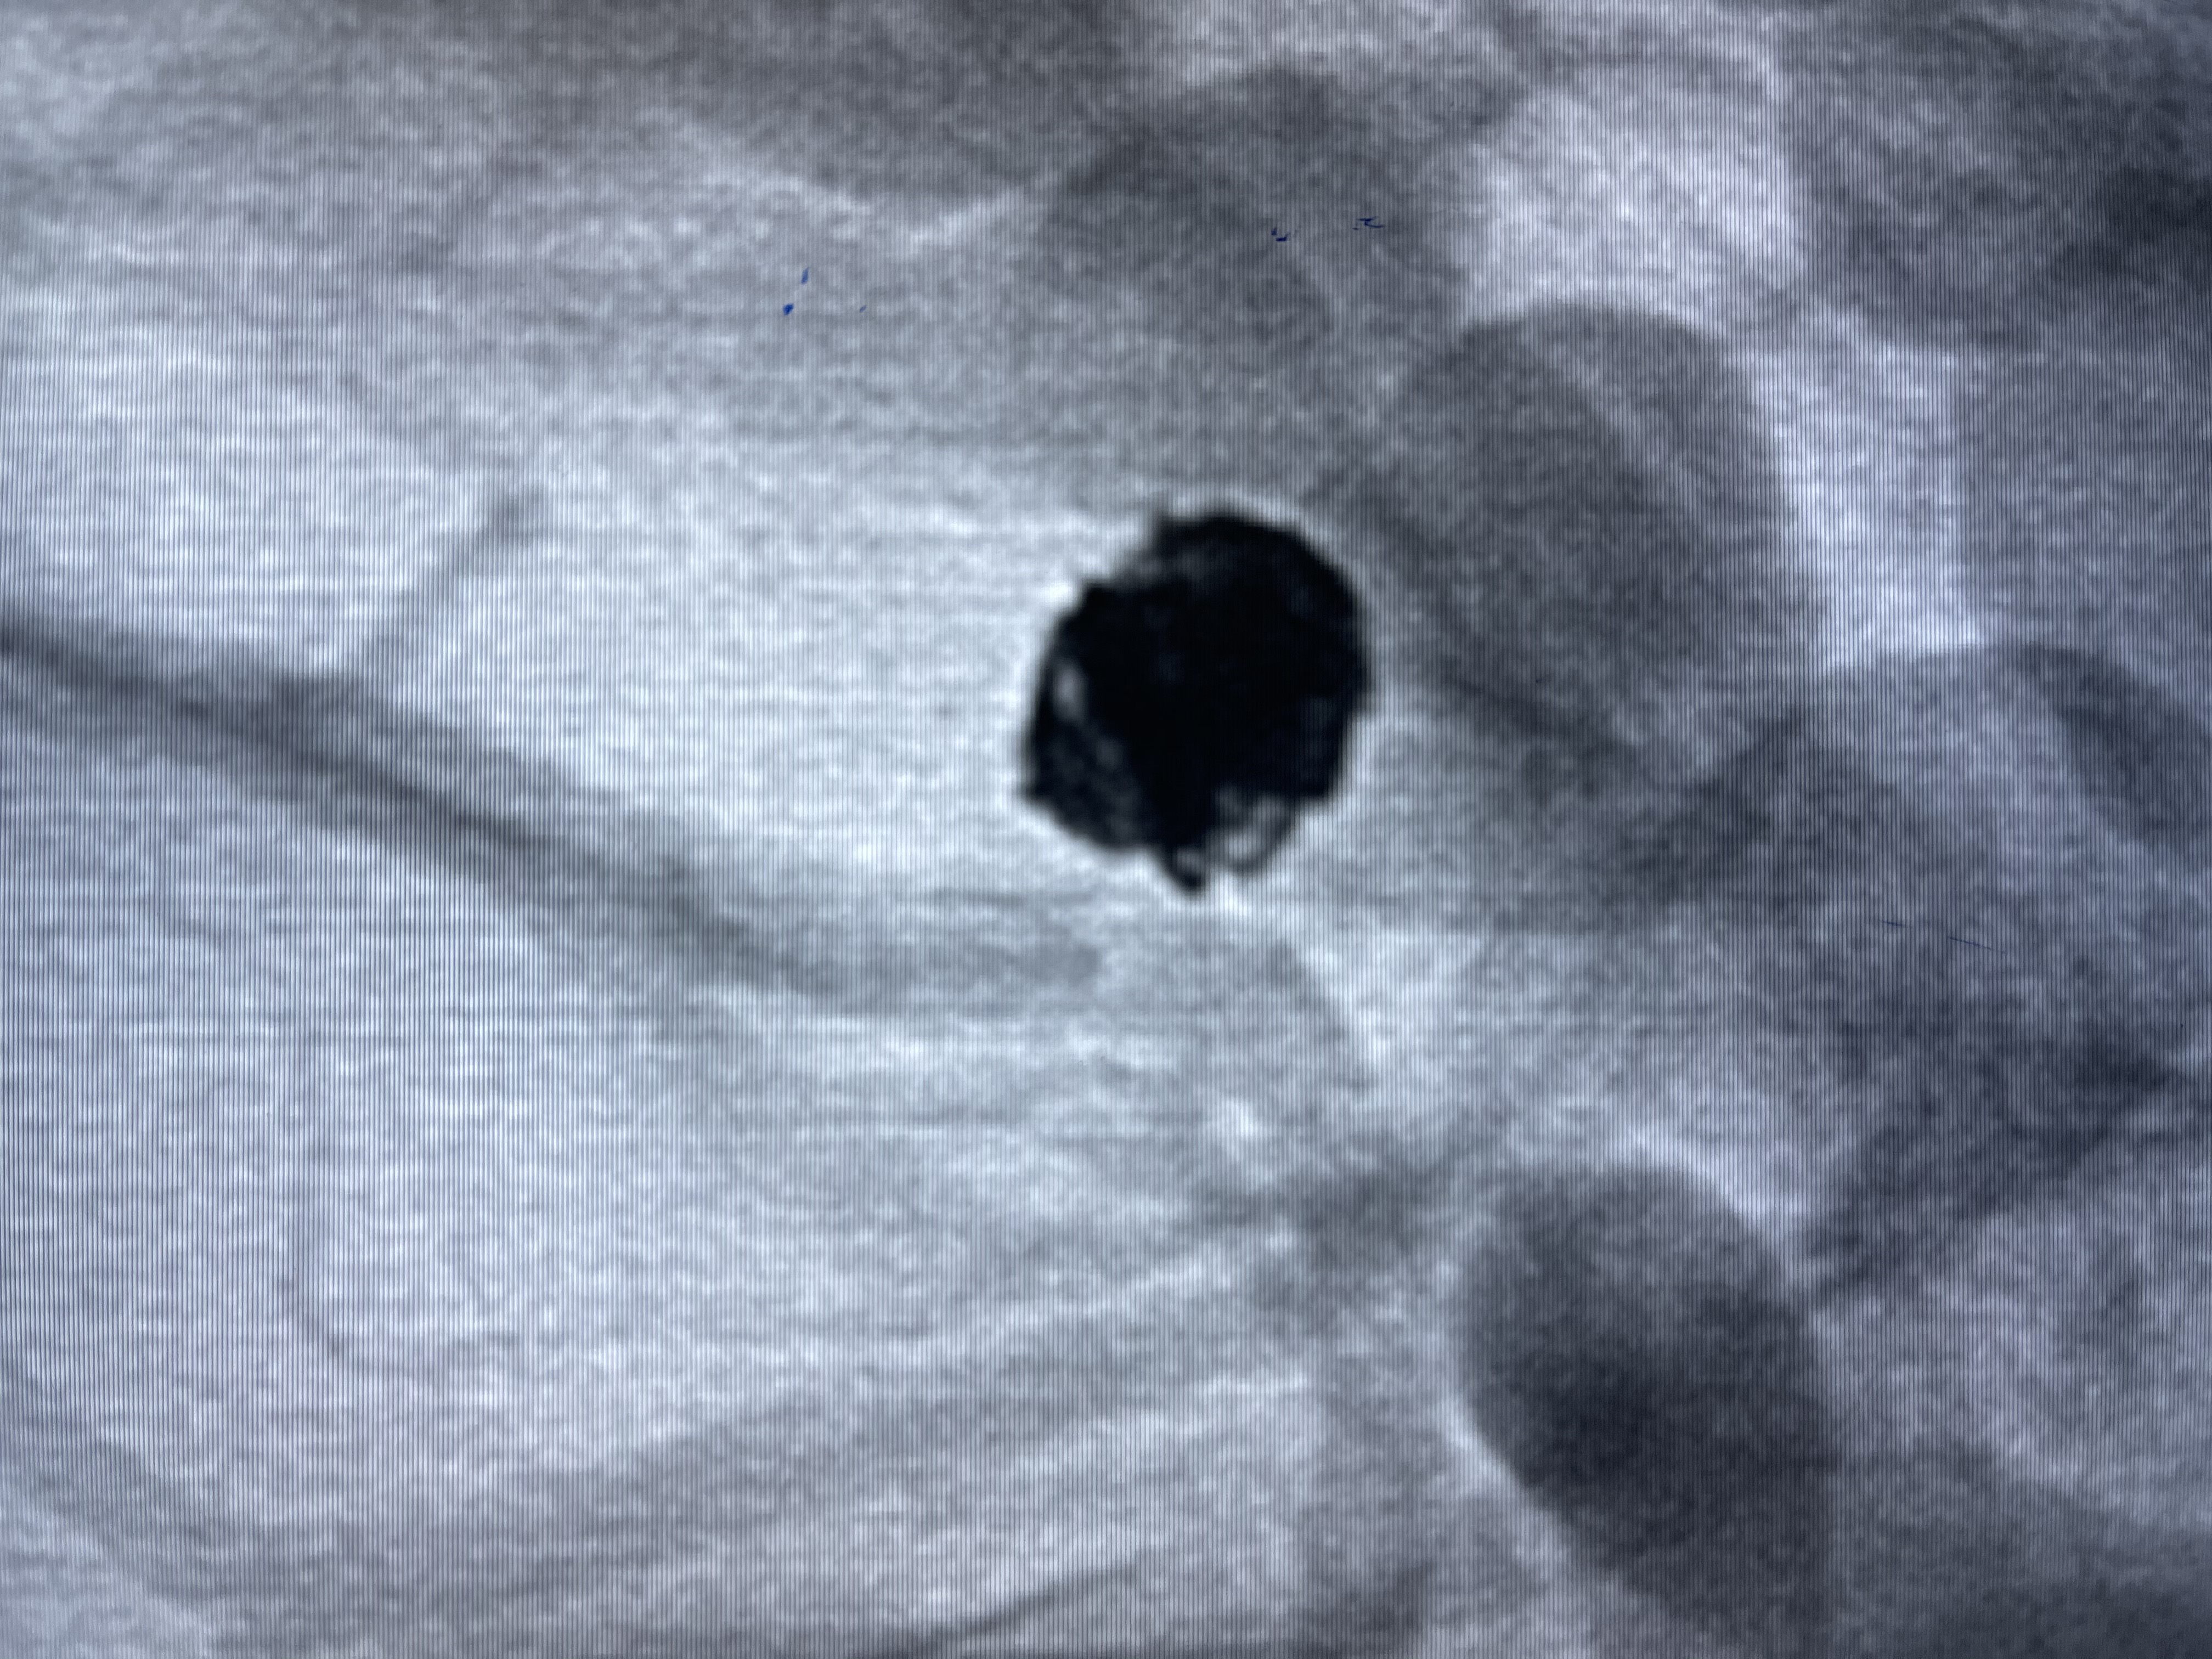

微弹簧圈尾端弹出动脉瘤,栓塞微导管轻轻送入动脉瘤内

1-4cm

1-2cm

动脉瘤致密填塞